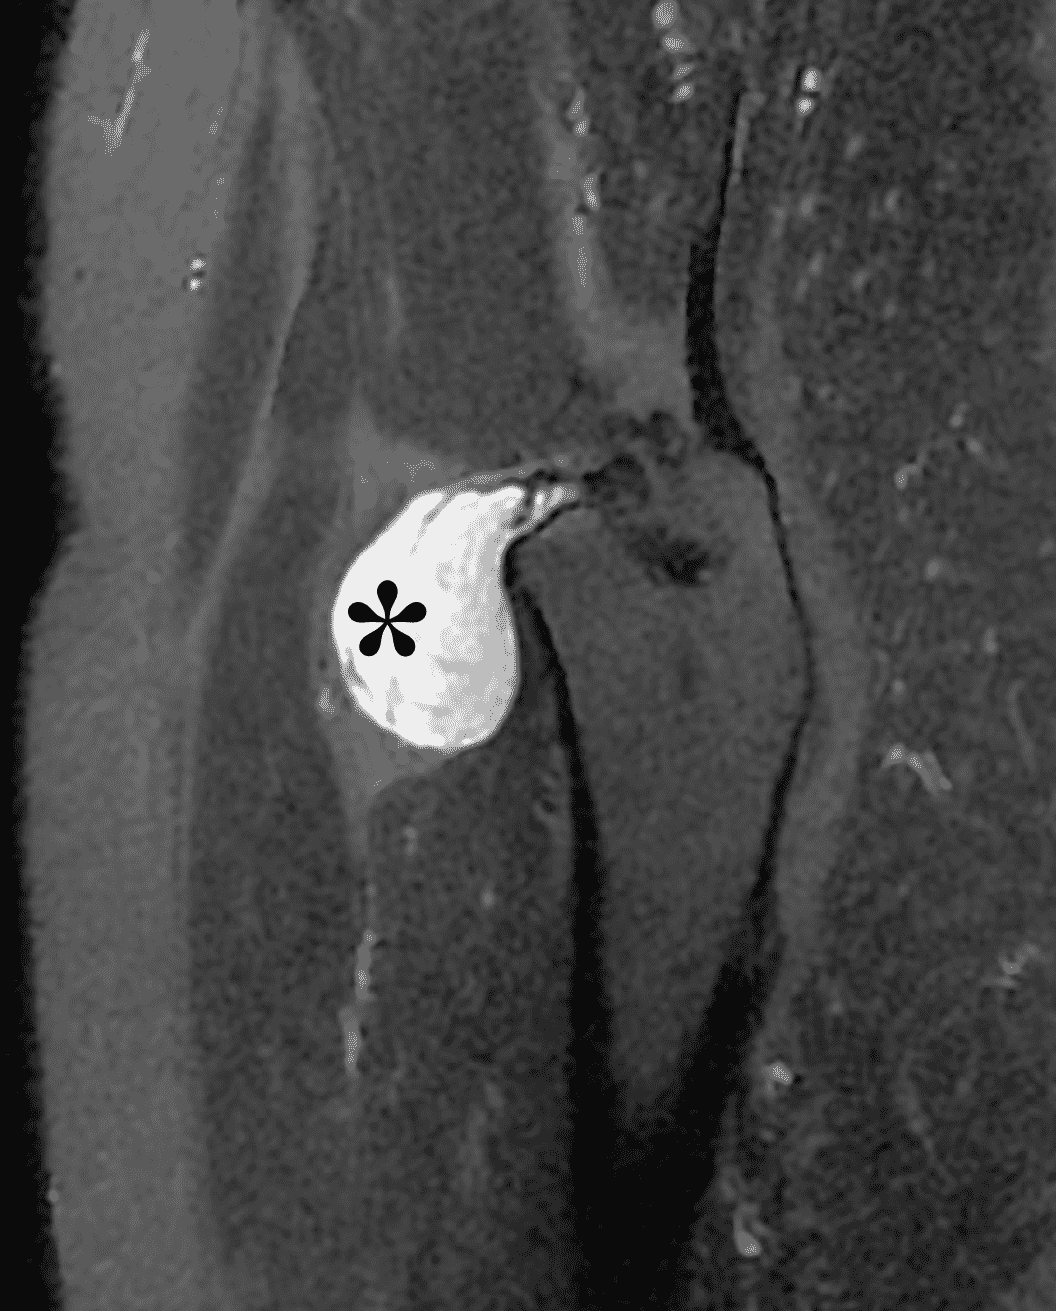

Juxta-articular Myxoma

Juxta-articular myxomas are mesenchymal tumors of uncertain etiology, and occur most commonly about the large joints, especially the knee. They have a male predilection and a large age range that peaks in the fourth to sixth decade. Patients may present with a palpable mass, swelling and pain. In general, juxta-articular myxomas demonstrate the same imaging and histologic characteristics of intra-muscular myxomas with a sharply marginated mass demonstrating myxoid type T2 hyperintensity, T1 hypointensity and thin variable amount of enhancement mostly in the periphery and septations (Figure 20). They may cause remodeling or erosion of adjacent bone and have a propensity to recur after resection.38,39

Figure 20: Juxta-articular myxoma of the hip. Sagittal (20A) fat-suppressed fluid-sensitive and (20B) post-contrast fat-suppressed T1-weighted images demonstrate a juxta-articular T2 hyperintense mass (asterisk) with thin, wispy septations and mild peripheral enhancement (arrow).